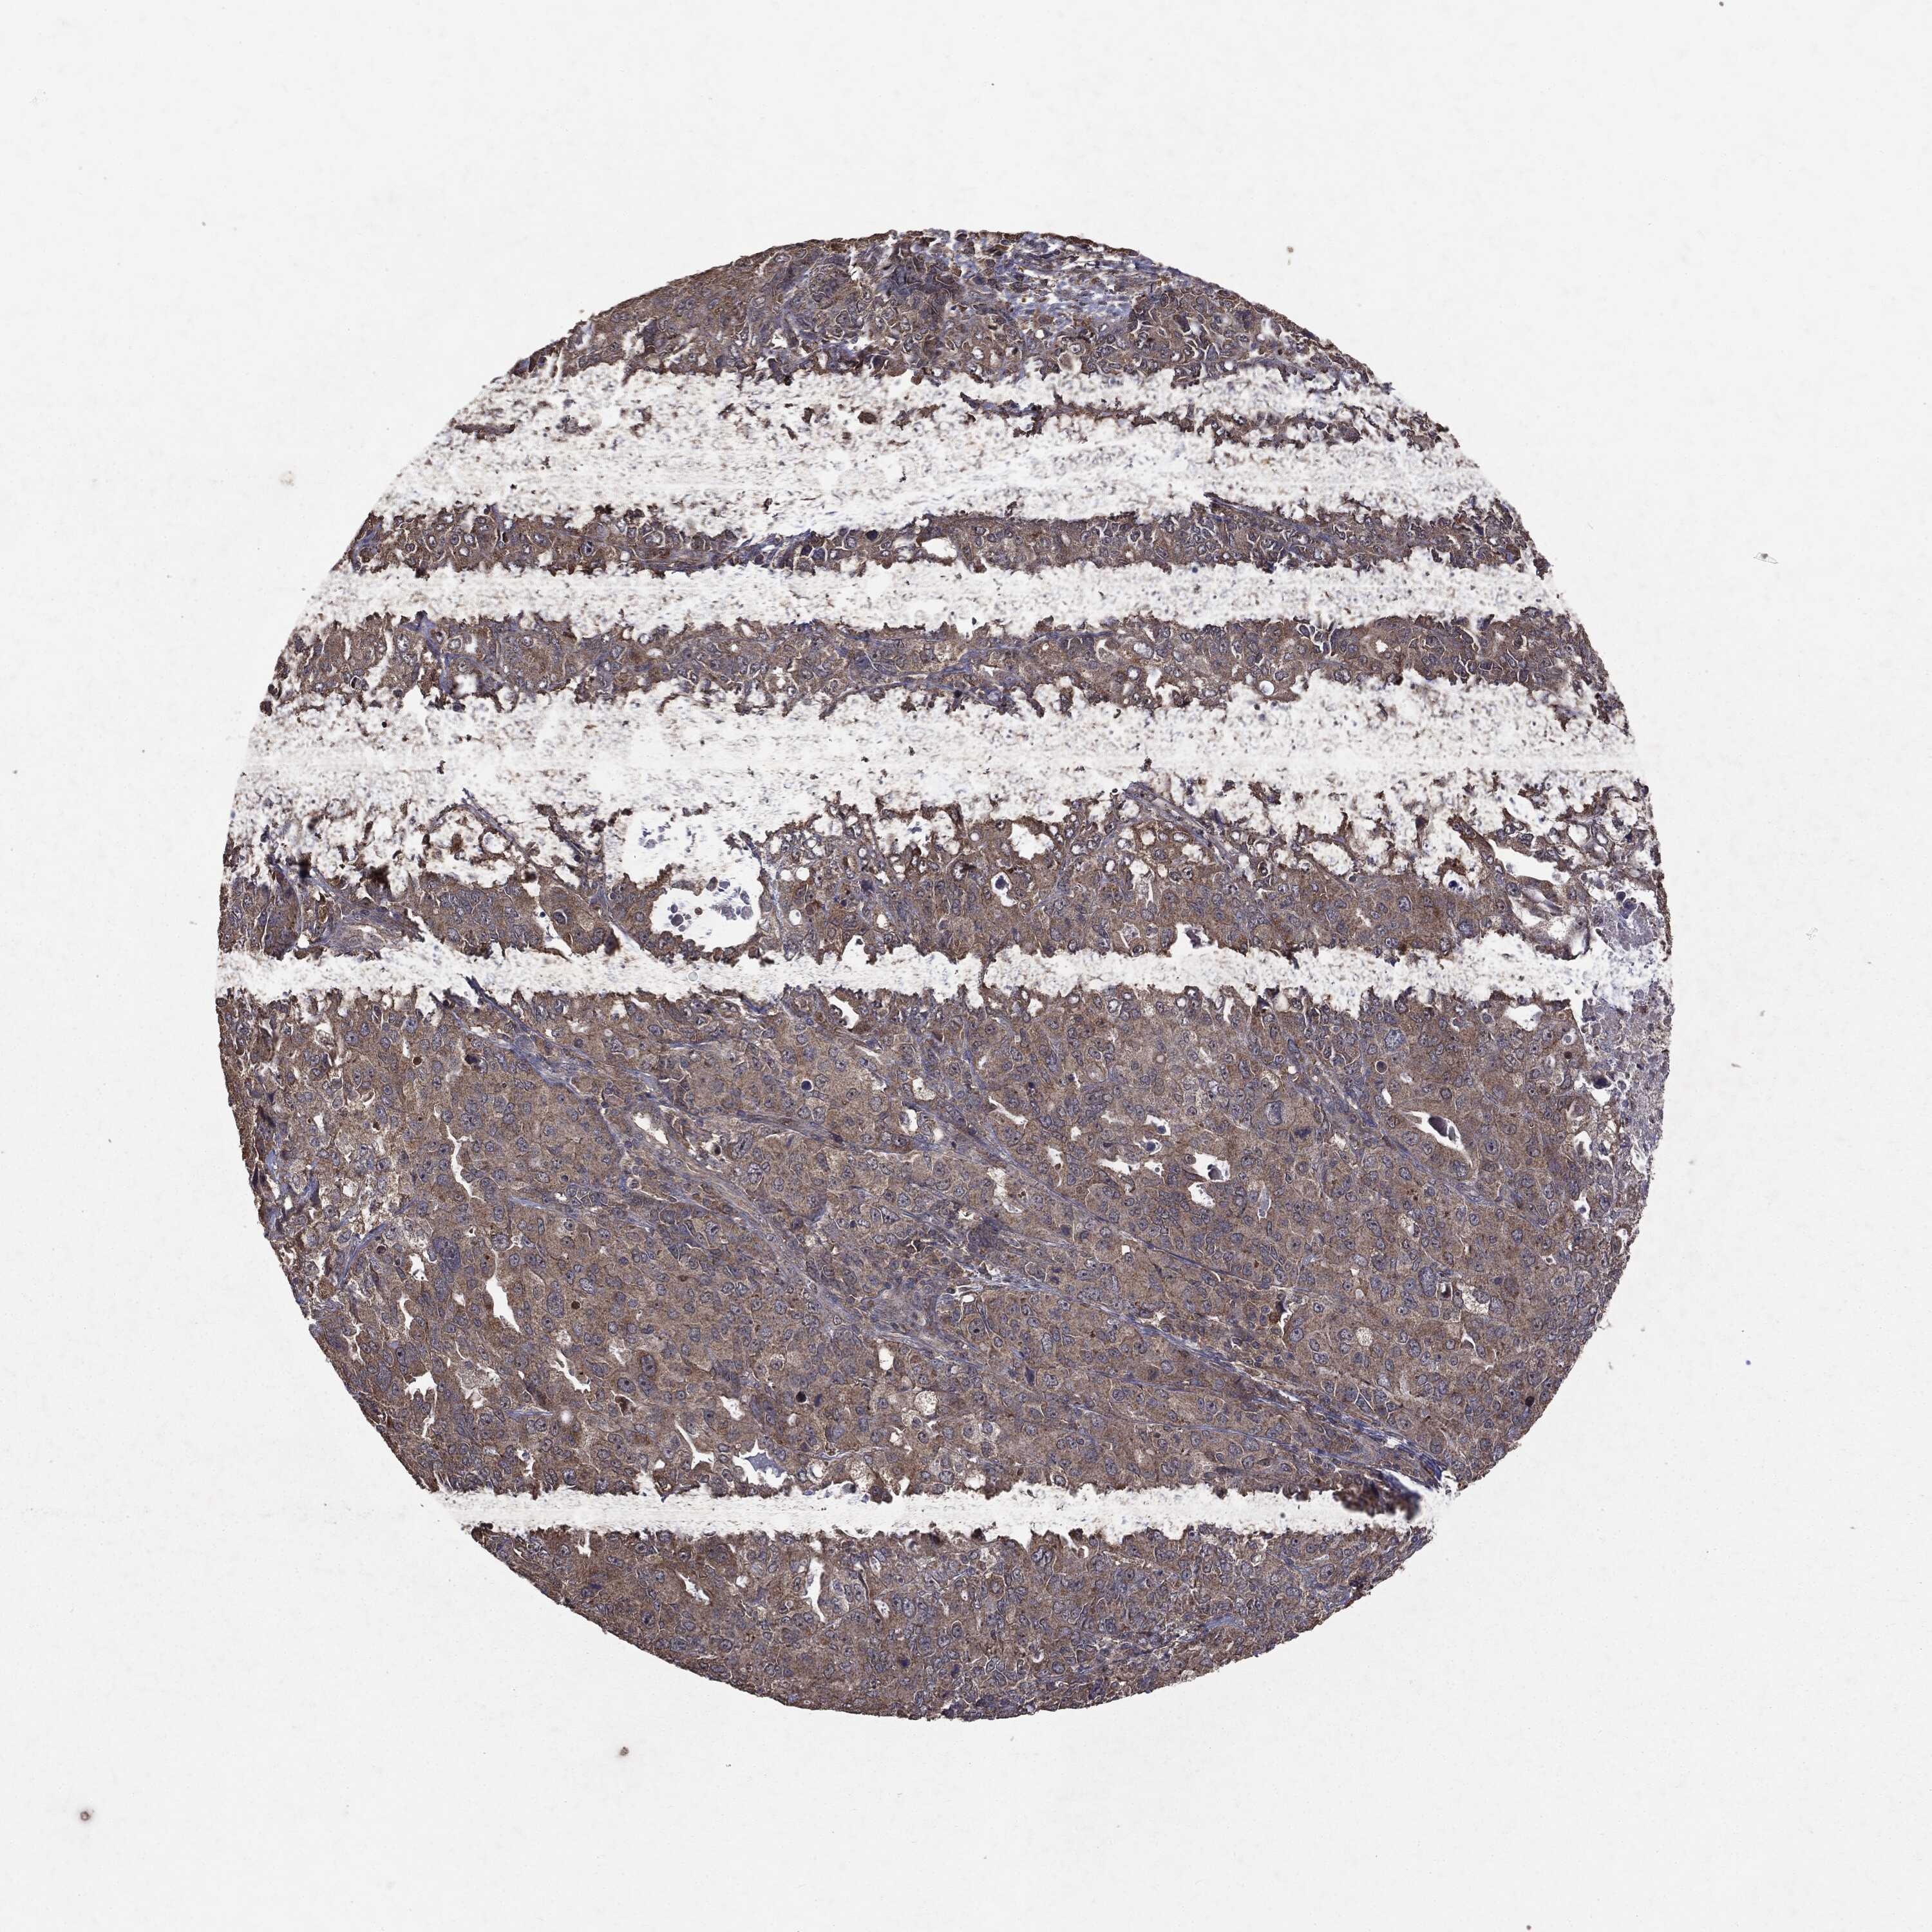

ENDOMETRIAL CANCER - Protein expressioni

A mouse-over function shows sample information and annotation data. Click on an image to view it in a full screen mode. Samples can be filtered based on level of antibody staining by selecting one or several of the following categories: high, medium, low and not detected. The assay and annotation is described here.

Note that samples used for immunohistochemistry by the Human Protein Atlas do not correspond to samples in the TCGA dataset.

Antibody stainingi

Antibody staining in the annotated cell types in the current human tissue is reported as not detected, low, medium, or high, based on conventional immunohistochemistry profiling in selected tissues. This score is based on the combination of the staining intensity and fraction of stained cells.

Each image is clickable and will lead to virtual microscopy that enables deeper exploration of all samples and also displays staining intensity scores, fraction scores and subcellular localization as well as patient and tissue information for each sample.

Antibody HPA031335

Antibody CAB004076

Antibody CAB080153

Antibody CAB080157

Staining

High

Medium

Low

Not detected

Intensity

Strong

Moderate

Weak

Negative

Quantity

>75%

75%-25%

<25%

None

Location

Nuclear

Cytoplasmic/membranous

Cytoplasmic/membranous,nuclear

Adenocarcinoma, NOS